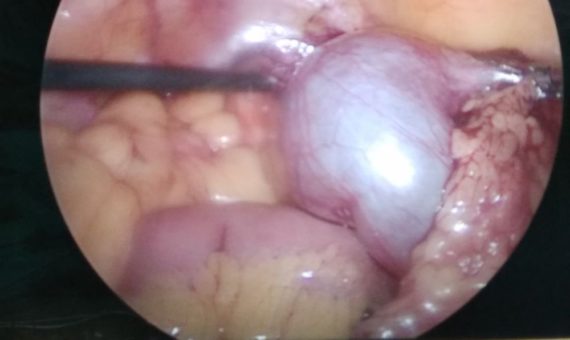

Patient came after 2 years of hysterectomy with constant abdominal pain. Sonography showed ovarian c [...]